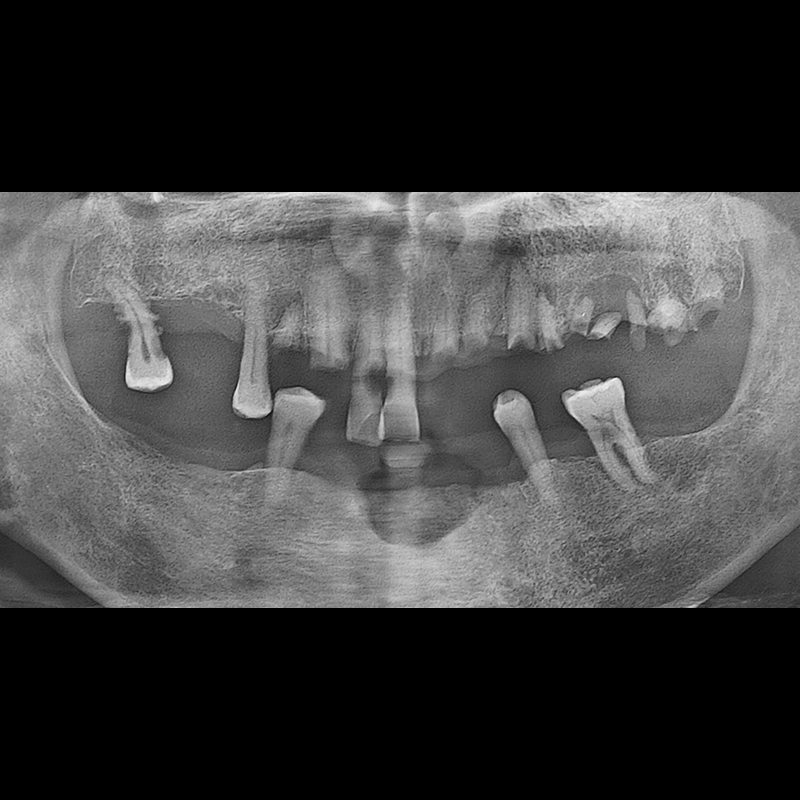

BEFORE AFTER

インプラント手術事例 2025.05.30

欠損した歯の部分と、生かしにくい歯の位置にインプラントを植立しました。